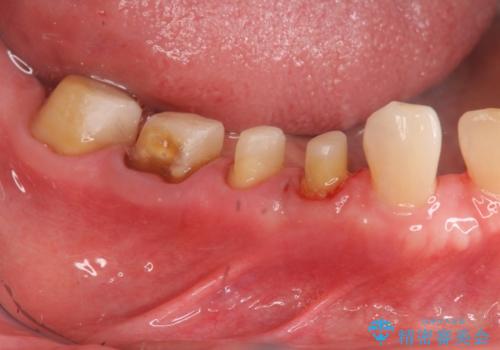

大臼歯 再根管治療

- 銀歯を白くしたいとの希望で来院されました。

せっかく銀歯を白くしても後々根管治療が必要になり、また壊して再治療を行うことを避けたいとの事でしたので、再根管治療から行っていきます。

ただ銀歯を白くするのではなく長期的な予後には歯の内部、根管治療の成功が必要不可欠です。